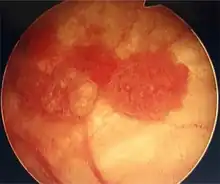

Currently, the best diagnosis of the state of the bladder is by way of cystoscopy, which is a procedure in which a flexible or rigid tube (called a cystoscope) bearing a camera and various instruments is introduced into the bladder through the urethra. The flexible procedure allows for a visual inspection of the bladder, for minor remedial work to be undertaken and for samples of suspicious lesions to be taken for a biopsy. A rigid cystoscope is used under general anesthesia in the operating room and can support remedial work and biopsies as well as more extensive tumor removal. Unlike papillary lesion, which grow into the bladder cavity and are readily visible, carcinoma in situ lesion are flat and obscure. Detection of carcinoma in situ lesions requires multiple biopsies from different areas of interior bladder wall.[53] Photodynamic detection (blue light cystoscopy) can aid in the detection of carcinoma in situ. In photodynamic detection, a dye is instilled into the bladder with the help of a catheter. Cancer cells take up this dye and are visible under blue light, providing visual clues on areas to biopsied or resected.[54]

Cystoscopy: multiple papillary tumors on the right side of the posterior wall -